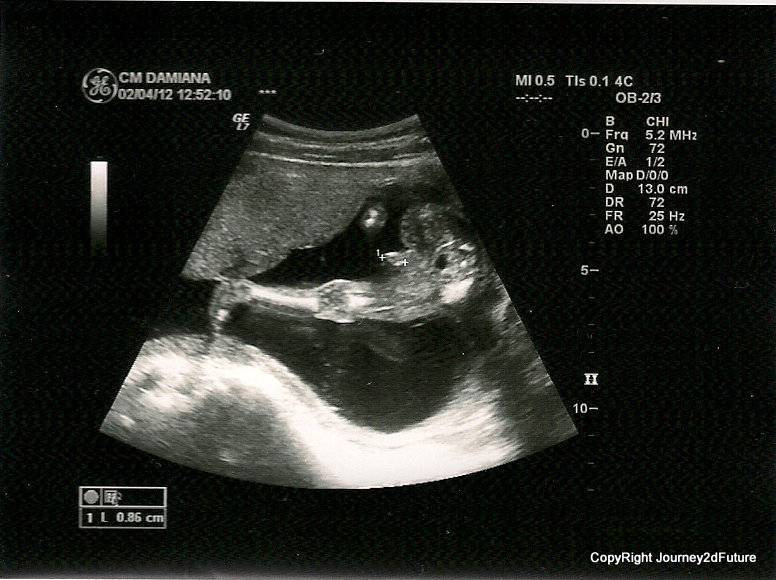

20 weeks Attachment 1883 12 weeks Attachment 1884 12 weeks Attachment 1885